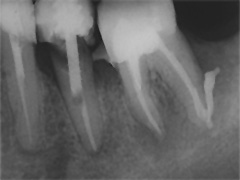

Der umfangreiche kariöse Defekt steuerte sehr bald hin auf die komplette Entfernung des Zahninnen­gewebes mit anschliessendem medikamentösen Wiederverschluss. Aufbissempfindlichkeit am Folgetermin ist immer Aufforderung zur erneuten Intensivsuche nach weiteren Kanälen, die hier einen 4. Ast zum Vorschein brachte. Nach 2 ausgelassenen Terminen

waren vorrangig Wiederherstellung von desinfizierender Einlage und provisorischer Füllung angezeigt. Eine weitere Woche später wurde in allen Kanälen das Medikament durch die endgültige Verschlussmasse ersetzt, worauf Zahn 36 mit 12-tägiger Verzögerung erneut zu rebellieren begann. Das hiess aus den hinteren Wurzeln Füllmaterial wieder raus und

Einlage erneut rein. Als es dann 4 Wochen später bei der hinteren Wur­zel aussen anzuschwellen begann und ein Medikamentenwechsel ohne Wir­kung blieb, wurden die hinteren Ka­näle abgefüllt und auch in gleicher Sitzung das überstopfte Material (Bild 1) mittels Resektion (Bild 2) von aussen entfernt.

Die ersten beiden Aufnahmen sind aus dem Jahr 1999, die 3. von 2006